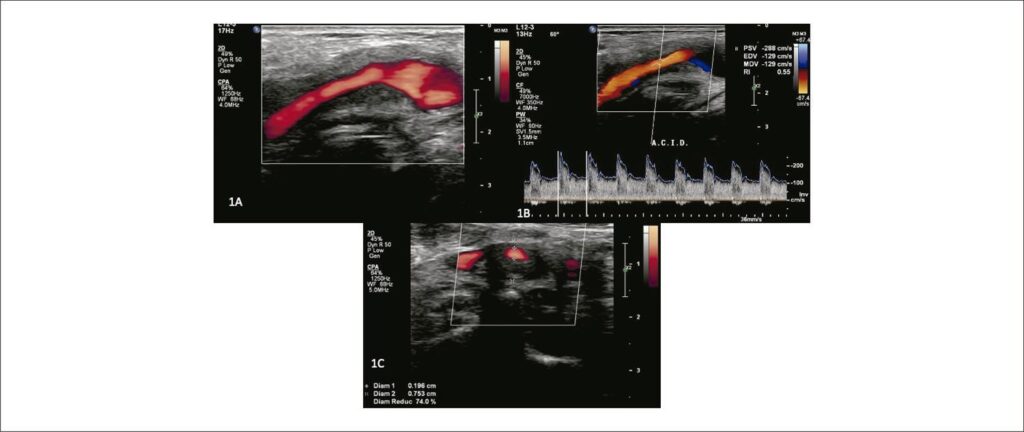

Given the clinical picture, a new VUS examination was requested, which included the standard protocol for evaluating the extracranial common, external, and internal carotid arteries (ACC, ICA and ACE). Special attention was given to extracarotid (perivascular) tissues due to the history of radiotherapy. The B-mode US showed extensive hypoechoic and homogeneous involvement of the tissues, including the arterial wall at the level of the carotid bifurcation, expanding to the proximal ICA (). The peak systolic velocity and end-diastolic velocity (PSV/EDV) were high: PSV/EDV = 288/129 cm/s (). Local stenosis measured in the transverse plane of the image was estimated at 74% (), consistent with the Doppler velocity data. The extent of the affected area was 5.57 mm compared to a lumen of 1.96 mm. Magnetic resonance imaging (MRI) and angioresonance (MRA) showed irregular thickening, with contrast enhancement, in the proximal ICA and bifurcation, corroborating the VUS findings ().